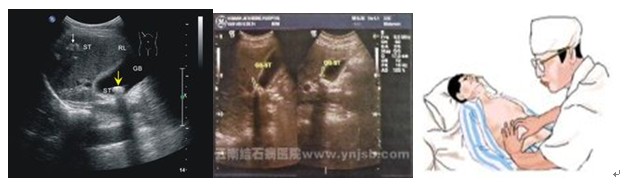

1、超声波检查 肝硬化时由于纤维组织增生,超声显示均匀的、弥漫的密集点状回声,晚期回声增强。肝体积可能缩小。如有门静脉高压存在,则门静脉增宽,脾脏增厚。